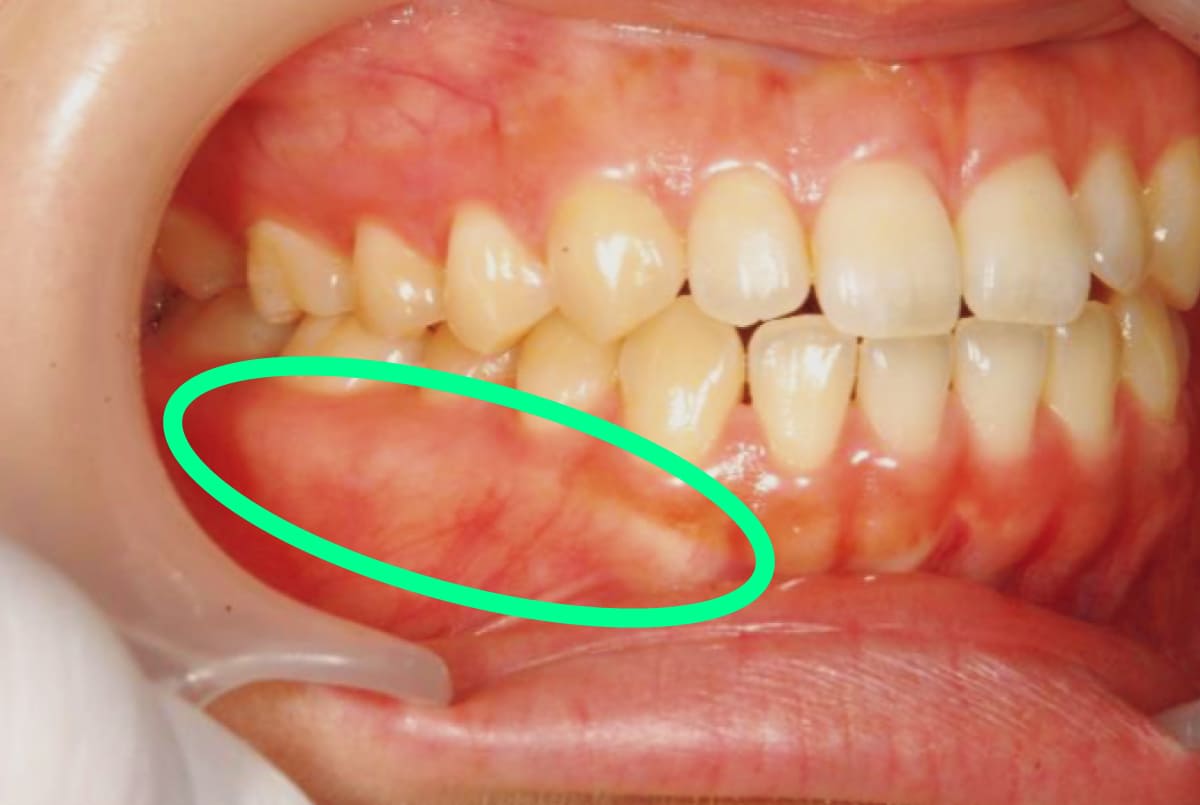

患者の主訴を受け、歯の咬耗や摩耗などがないか確認。エビデンスは乏しいが、長期間にわたる過度な力の影響で、下顎の内側や外側の骨、上顎の中央部に骨が隆起することも(写真1枚目)。また頰粘膜や舌につく圧痕(写真2枚目)もポイント。歯科検診でこれらの状況が確認され、歯科医師がブラキシズムの可能性を示唆する場合もある。